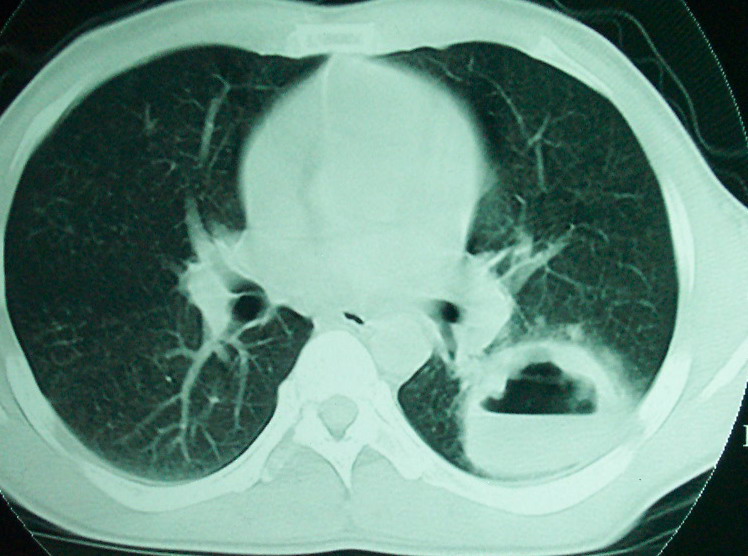

m      37y      发热   咳脓痰月余      ct肺脓肿但住院抗炎治疗后双肺内结节不知该如何解释

治疗后见左肺下野病灶较前缩小但双肺内结节影似无变化请较各位老师该如何下结论    治疗前wbc14.5 治疗后wbc 11.0

血源性肺脓肿,一般由原发感染灶引起脓毒败血症,在肺部形成小脓肿,病变变化快,容易形成肺气囊,脓气胸,主要与转移瘤鉴别,通过临床病史可分

左下肺病灶除了明显的厚壁空洞 气液平外,明显见壁结节,另两肺多发小结节,综合考虑:左下肺周围性肺癌伴肺内转移.

如果你仔细的同层面对比,你会发现所有的病灶均有比较明显的吸收、缩小。病变的形态,特别是脓肿的形态、壁的厚薄、内壁均有很大的变化,均在往好的方面发展。与临床症状、血像均符合,治疗效果比较显著,就是肺脓肿并双肺的化脓性炎症灶。